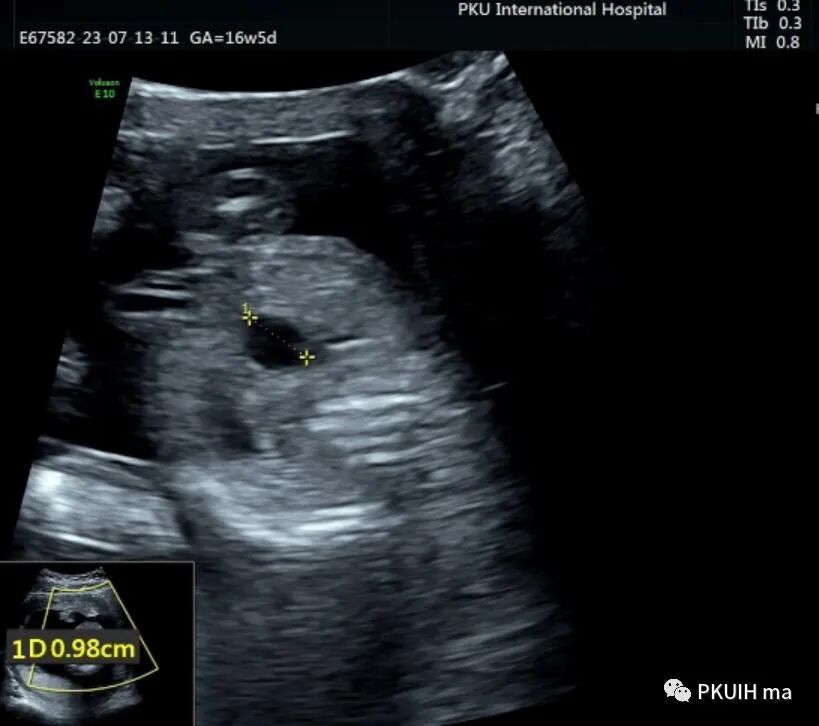

孕妇16周+5天常规超声检查发现腹部一囊性包块,如下图

胎儿中腹部见一囊性包块,大小约1.2x1.0x0.8cm,边界清,形态规则,内透声好。囊肿位于脊柱前方、胆囊后方、门静脉窦旁,与后肾接近

观察囊肿与肾、胃泡、膀胱均无相关。

仔细观察囊肿壁好像不完整,周边见微小管道回声与囊肿相通

CDFI:囊肿内未见明显血流信号。

由于囊肿位于胆囊后方、肝下方、门静脉窦旁,随考虑为胆总管囊肿